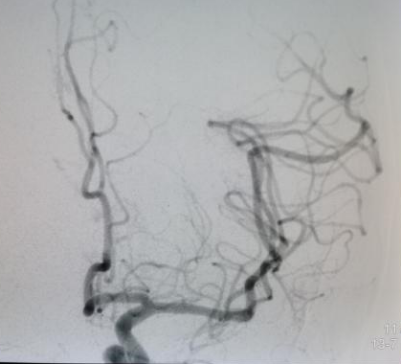

手术由魏华明主治医师操作,10分钟完善术前准备,导管室护士和麻醉师迅速到位,30分钟置鞘成功,40分钟完成脑血管评估,2小时内完成大脑中动脉再通(图二)。术后患者右侧肢体即刻能活动(图三)。术后,神经内一科护理团队密切监护,患者平稳度过7天脑水肿期,现病人言语清楚,右下肢肌力能达到5-级,于3月12日康复出院(图四)。